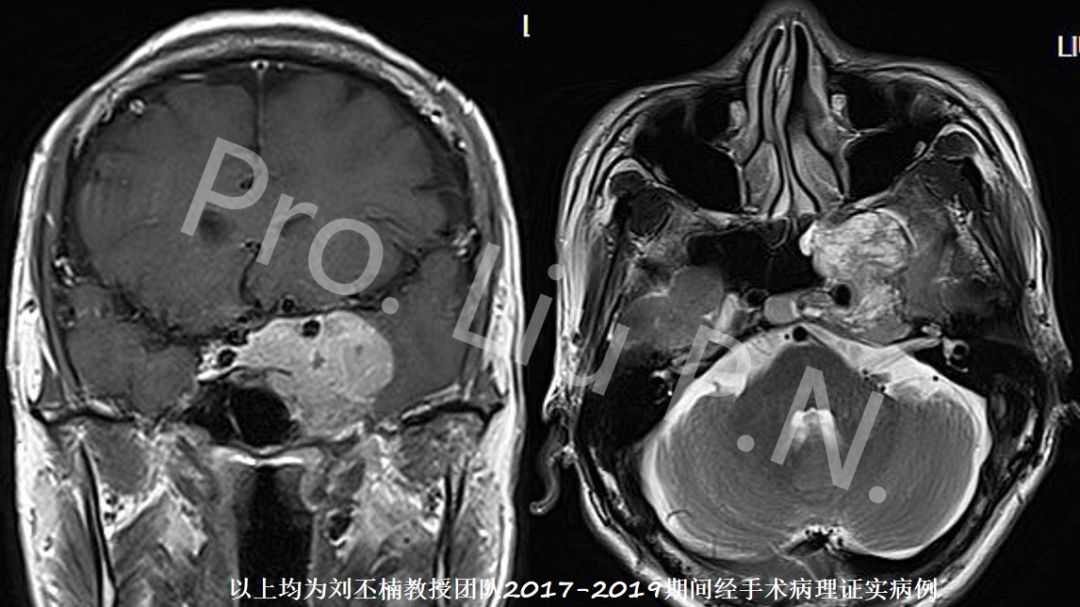

六、扩大经蝶窦入路手术案例

--侵袭性垂体瘤

![]()